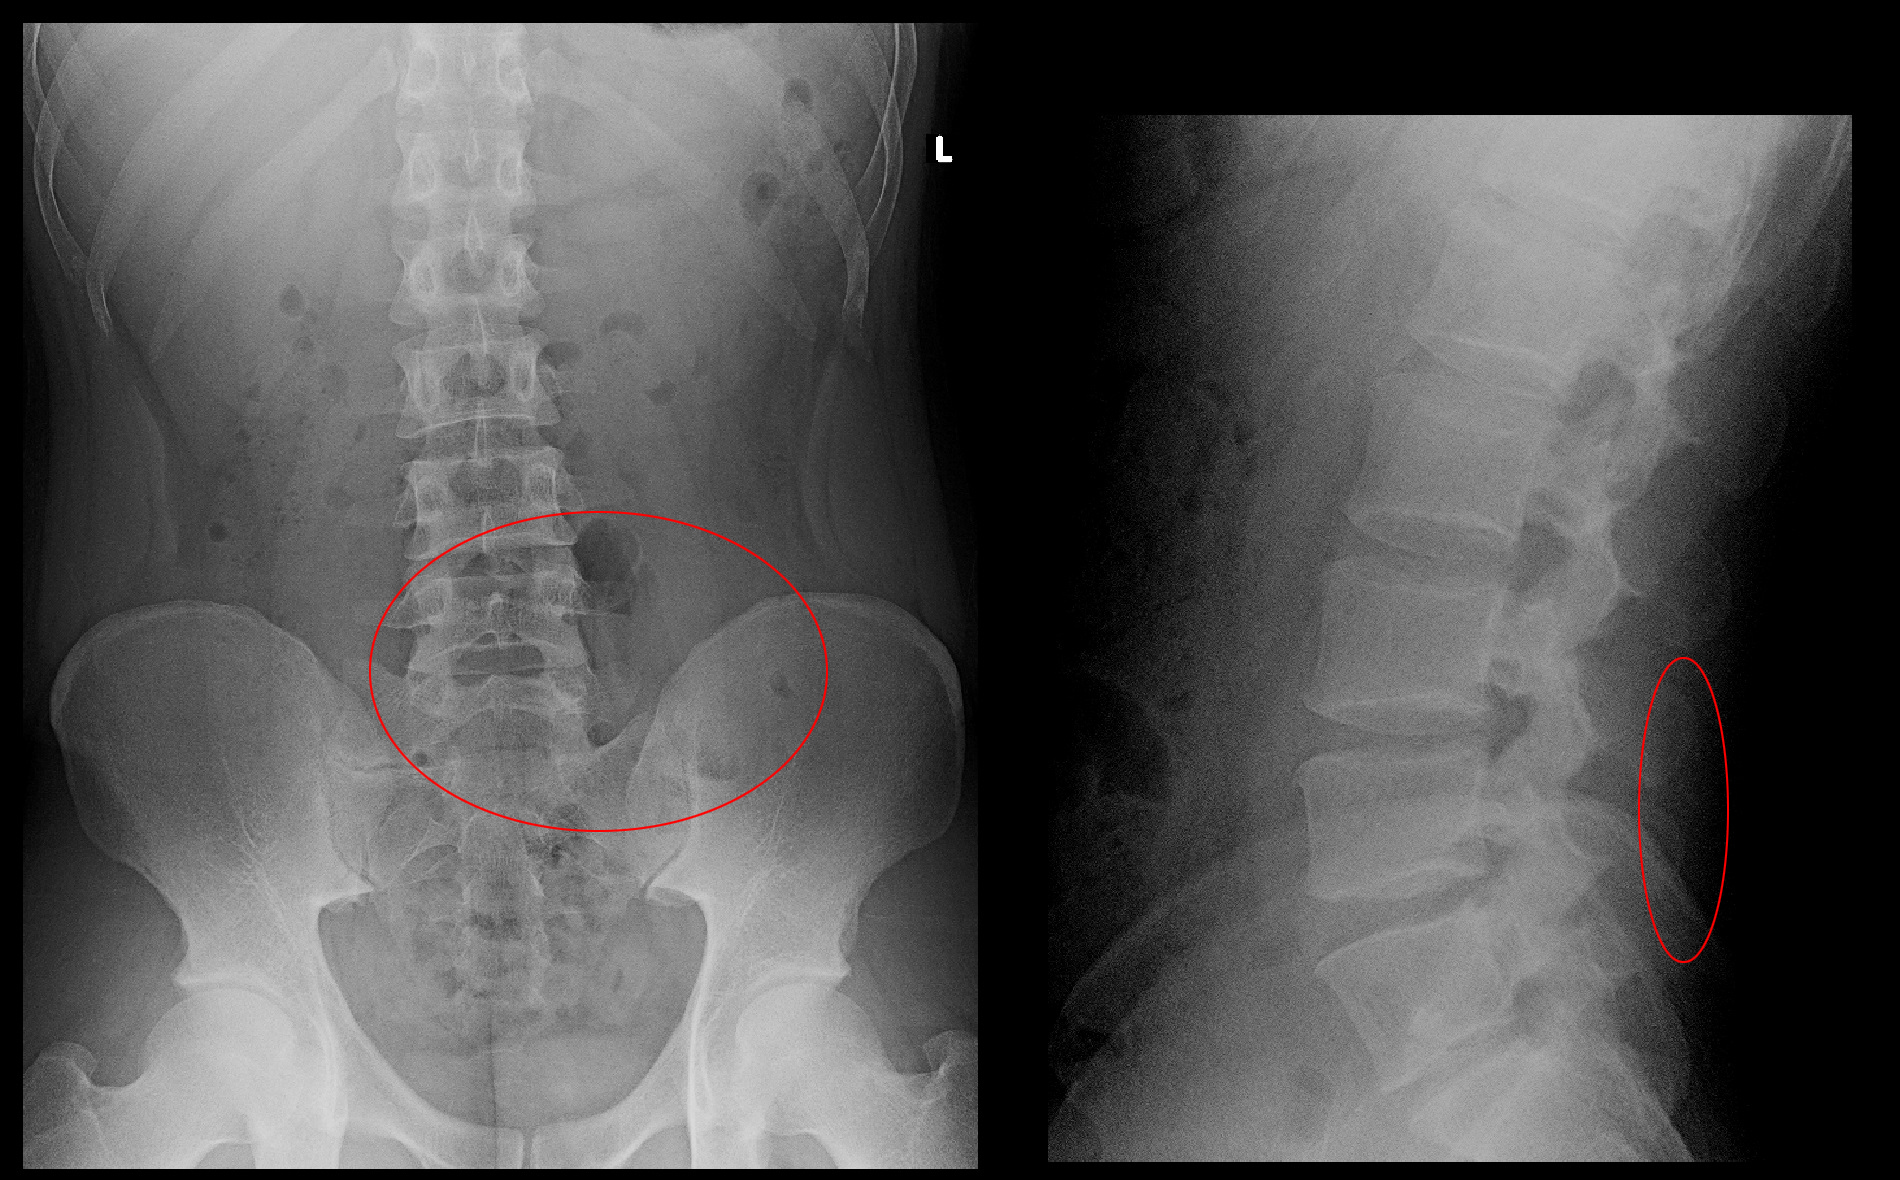

25才男 MR1.jpg

MRI検査の横からみた画像(矢状断)ではL5Sの椎間板ヘルニア(オレンジ矢印)が目立ちますが、右側の水平断(横断面)ではL5Sは丸い横断面の脊髄と椎間板ヘルニアの境界は離れています。しかし、L45では脊髄の前方(画像では上方)は軽度凹む状態となっており、左側よりでヘルニアと脊髄は密着しています(赤矢印)。また、T1矢状断(上欄中央画像)ではL5Sのヘルニアと後方の脊髄の境界は黒い線が確認されますが、L45ではわずかに椎間板が(L34に比較して)グレーに後方に出ており黒い脊髄との境界は不鮮明です。境界が黒く鮮明なのは古いヘルニアを示し、境界が不鮮明な椎間板は最近発生したヘルニアと私は判断しています。

そこで患者さんの希望も確認して、L45高位で左側の神経根ブロックを行いました。薬も10日分処方しています。